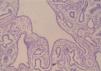

CASO CLÍNICOFeto varón (IVE) de 20 semanas de gestación, que pesaba 645g y medía 30cm. El examen externo mostraba una maceración corporal en grado moderado, y no eran evidentes malformaciones externas. La apertura de cavidades permitió el flujo de líquido seroso en cuantía elevada, principalmente a nivel de la cavidad peritoneal. En el tórax se observó un evidente desplazamiento mediastínico hacia la derecha debido a la presencia de un pulmón izquierdo de gran tamaño a expensas del lóbulo inferior (el de mayor tamaño si bien el aumento de tamaño era generalizado) (figs. 1 y 2). Ese pulmón pesaba 10g en relación con los 4,5g del pulmón derecho. Al corte se apreciaba un parénquima blanquecino de consistencia firme-elástica, con un tenue patrón nodular (fig. 3). El resto de las vísceras torácicas y abdominales no mostraban alteraciones macroscópicas significativas. El estudio microscópico del pulmón izquierdo demostró la presencia panlobar de una lesión constituida por múltiples quistes de pequeño tamaño (figs. 4 y 5) de contornos polimorfos tapizados por un epitelio cúbico, focalmente ciliado sin atipias citológicas (figs. 6 y 7). Esa lesión ocupaba la totalidad del parénquima pulmonar homolateral sustituyendo la histología pulmonar correspondiente a esta fase del desarrollo visceral. Con tales hallazgos y realizando un estudio conjunto de las características clínicas y de imagen, se llegó al diagnóstico de hiperplasia adenomatosa pulmonar de grado III. Otros hallazgos de interés fueron una inmadurez visceral generalizada y la presencia de focos hematopoyéticos extramedulares (hígado y bazo), correspondientes a la edad gestacional. El cordón, las membranas y la placenta no mostraron alteraciones de relevancia.

Tipo III: se trata de la variante más sólida y extensa de las tres, y puede afectar tanto a un solo lóbulo como a la totalidad del parénquima pulmonar. Así, al corte, se observa un gran número de pequeñas estructuras quísticas asociadas o no a arterias bronquiales. Los quistes, de pequeño tamaño, están recubiertos por un epitelio cuboideo ciliado; la capa fibromuscular que los rodea es delgada y rica en elastina; en cambio, no se observan estructuras cartilaginosas asociadas.